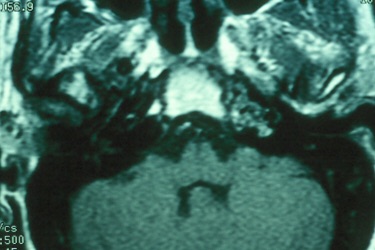

The petrous apex is a relatively inaccessible area that can occasionally harbor serious disease. Disease processes that usually cause symptoms are typically inflammatory or neoplastic in nature. Petrous apex lesions typically cause nonspecific symptoms such as headache, but as the lesion becomes more extensive, adjacent structures such as cranial nerves can become involved. A common early and specific sign of a petrous apex process is abducens palsy. Current imaging techniques can usually provide enough supplemental information to allow a focused plan of treatment. It is important to determine whether a petrous apex lesion can be observed or, if surgical treatment is required, whether a drainage or excision is required. There are various available surgical approaches to the petrous apex. The choice depends on the status of hearing function as well as the suspected pathology, which will dictate whether a drainage or excisional procedure is required.

- Summarize the types of pathology that can occur in the petrous apex, the imaging required, and proper interpretation of information so that a proper differential diagnosis can be formulated.